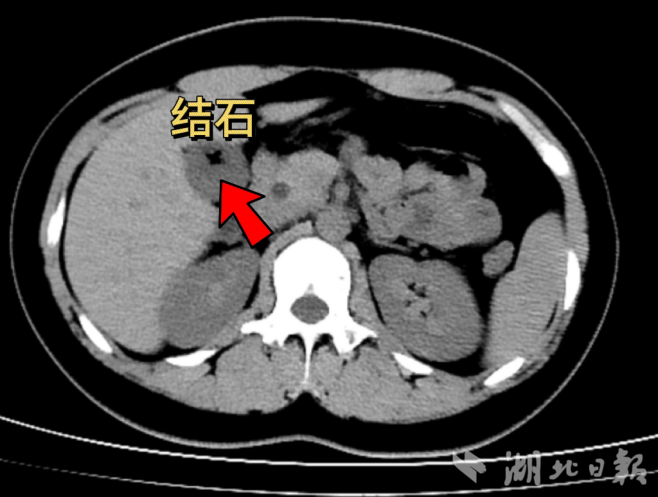

考虑到小袁年纪轻轻,其家属也强烈希望保留胆囊。李纯坚经过系统检查,并结合术前检查提示的胆囊收缩功能以及优化胆汁的功能还存在,确认小袁的胆囊功能尚好,符合保胆取石术的条件,于是果断选择给患者施行保胆取石术。在腹腔镜和胆道镜微创技术下,成功取出了胆囊内六枚板栗大小结石。整个手术过程顺利,小袁术后恢复迅速,次日便能下床活动,疗养几日后便康复回归正常生活。